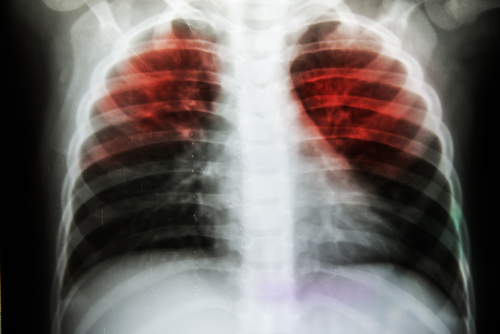

According to a recent study, scientists have pinpointed a chemical signal that worsens inflammation linked to a life-threatening lung condition.

The study was published in journal Thorax.The researchers feel that this discovery could lead to new therapies for the disease, which can be fatal for up to half of those affected.Acute Respiratory Distress Syndrome (ARDS) is caused by widespread inflammation in the lungs and can lead to fluid leaking into the airways.The researchers found that patients with ARDS had high levels of a type of molecule called mitochondrial formylated peptide in the fluid of their lungs.

The lab tests found that these molecules play a key role in attracting specialised immune cells called neutrophils.Neutrophils are known to be responsible for orchestrating the inflammation associated with ARDS.Recent studies with mice found that blocking the molecules' signalling mechanisms helped to stem neutrophil infiltration and alleviate lung inflammation associated with ARDS.ARDS affects patients who are already critically ill and can be triggered by severe injuries or infections such as pneumonia.The researches explained, therapies that target these molecules, could potentially help patients with any type of ARDS, whether caused by an infection or not.

“For the first time, we have demonstrated that these mitochondrial formylated peptides are present and elevated in ARDS and that they directly drive lung inflammation. This therefore highlights a potential novel therapeutic target for this life threatening illness,” said study’s lead author Professor Adriano Rossi, of the University of Edinburgh's MRC Centre for Inflammation Research.